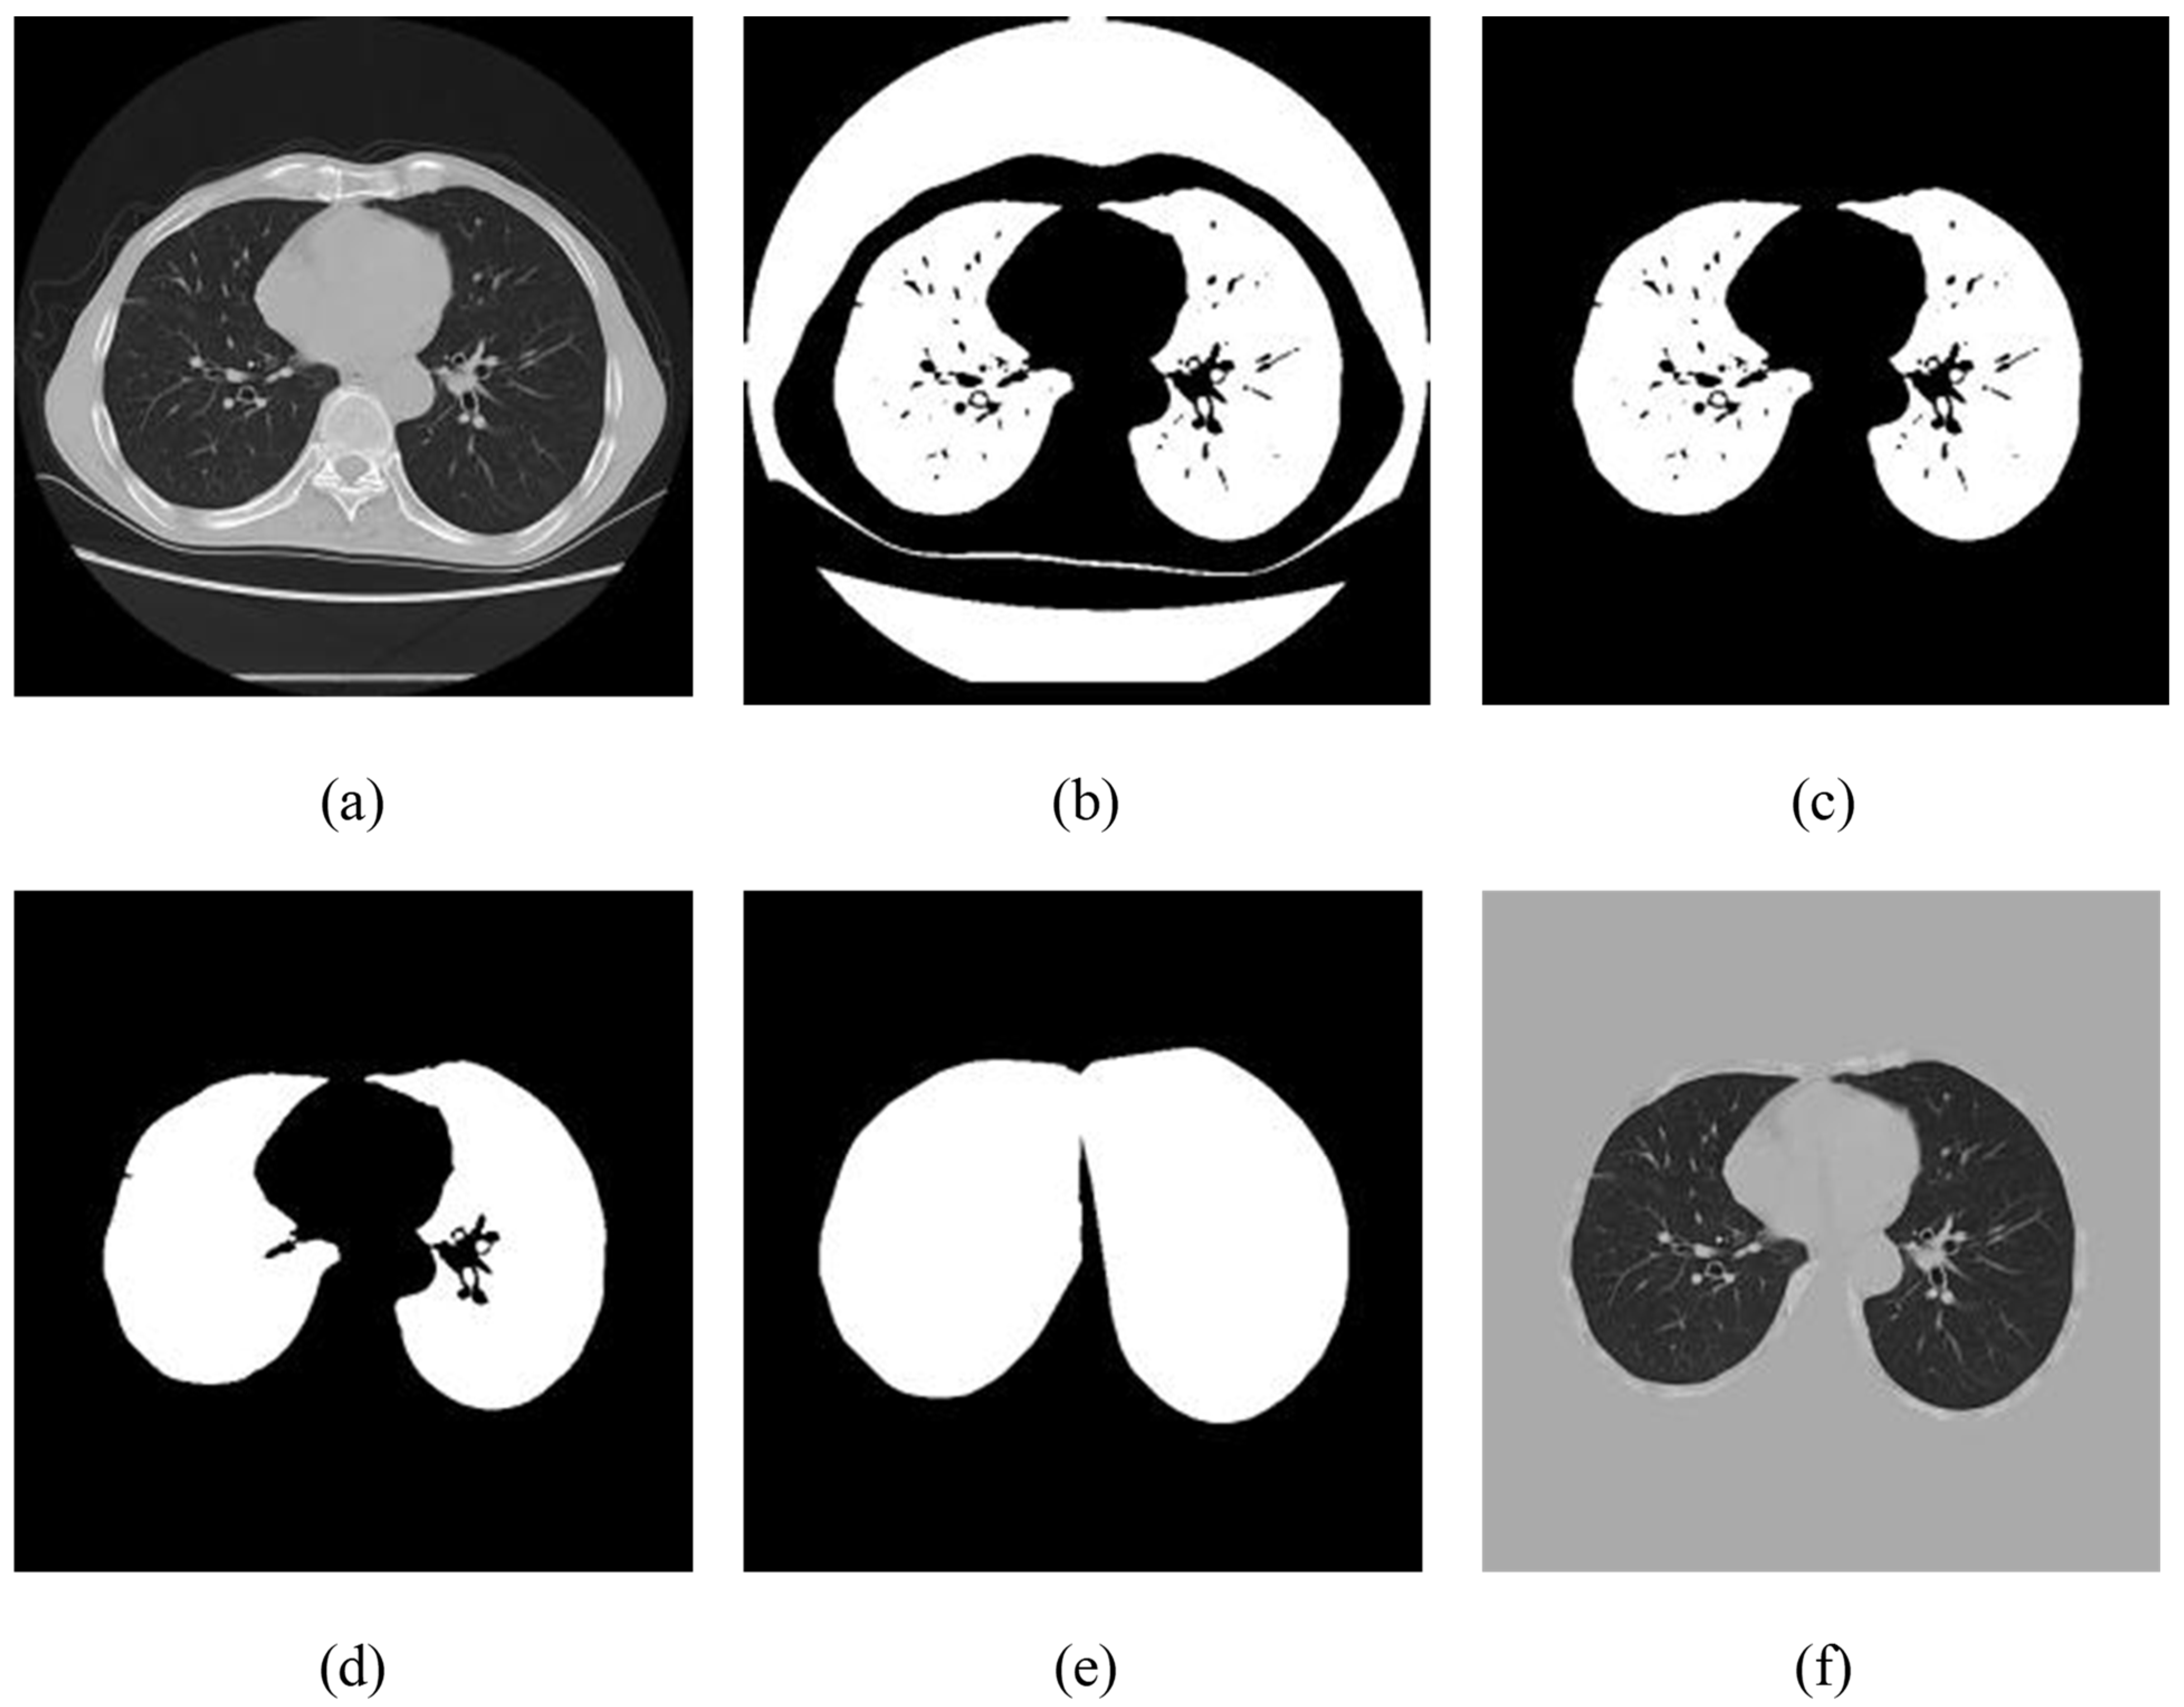

- As the advanced grayscale image was ranging in pixel estimates (0, 255), the retuned raw data of the CT image was appropriately transformed from the Hounsfield unit (HU) to the aforementioned properties. The HU data frame was truncated to within (−1200, 600) (any value other than this was set to −1200 or 600) and then standardized to (0, 255), directly corresponding to the digital format as presented in Figure 3a.

- A fixed range (−600) was used to remove or binarize the returned computed tomography images, and delicate bones and tissues, e.g., nerves and muscles, were filtered with considerable HU values Figure 3b.

- Each associated segment smaller than 0.3 cm2 and more than 0.99 unpredictable was ejected to remove some noise from high-brightness spiral imaging. The segment (usually clothes and ancillary equipment other than the human body) was also evacuated with center point separation of the CT image over 7 cm. In addition, segments with volumes of 450 and 7500 cm3 were retained, as seen in Figure 3c. In the current investigation the range was increased to the contrary and those who announced the discovery of the lung knob were 22, which ranged from 680 to 75% cm3. Knob detection study typically focuses on small spots, while viral infection can be progressively for COVID-19 cases.

- In step 3, the mask disintegrated into two separate regions and then expanded to the original shape to remove the small black spots Figure 3d.

- High-structure activity, i.e., convex hull operation was performed on the effective region to include areas of viral disease associated with the external mass of the lung, which had been removed from previous advances.

- Image matrix data from step 1 was replicated by the exchanged masks from step 5 to obtain the final powerful aspiration region for further preparation. The region outside the mask was filled with 193, which was proportional to 0 when it returned to the HU estimate as Figure 3f.